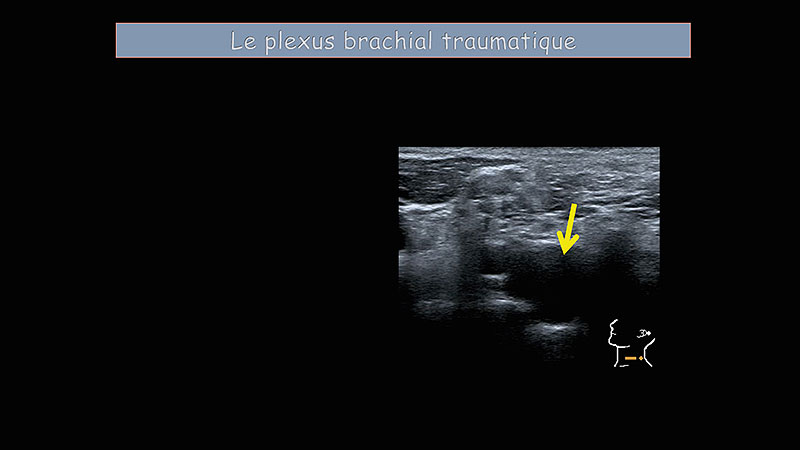

Plexus nerveux et creux axillaire

M Faruch Bilfeld, F Lapègue, H Chiavassa Gandois, N Sans